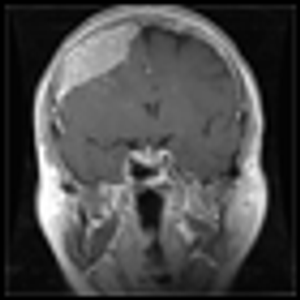

Intracranial neoplasms can arise from any of the structures or cell types present in the cranial vault, including the brain, meninges, pituitary gland, skull, and even residual embryonic tissue.